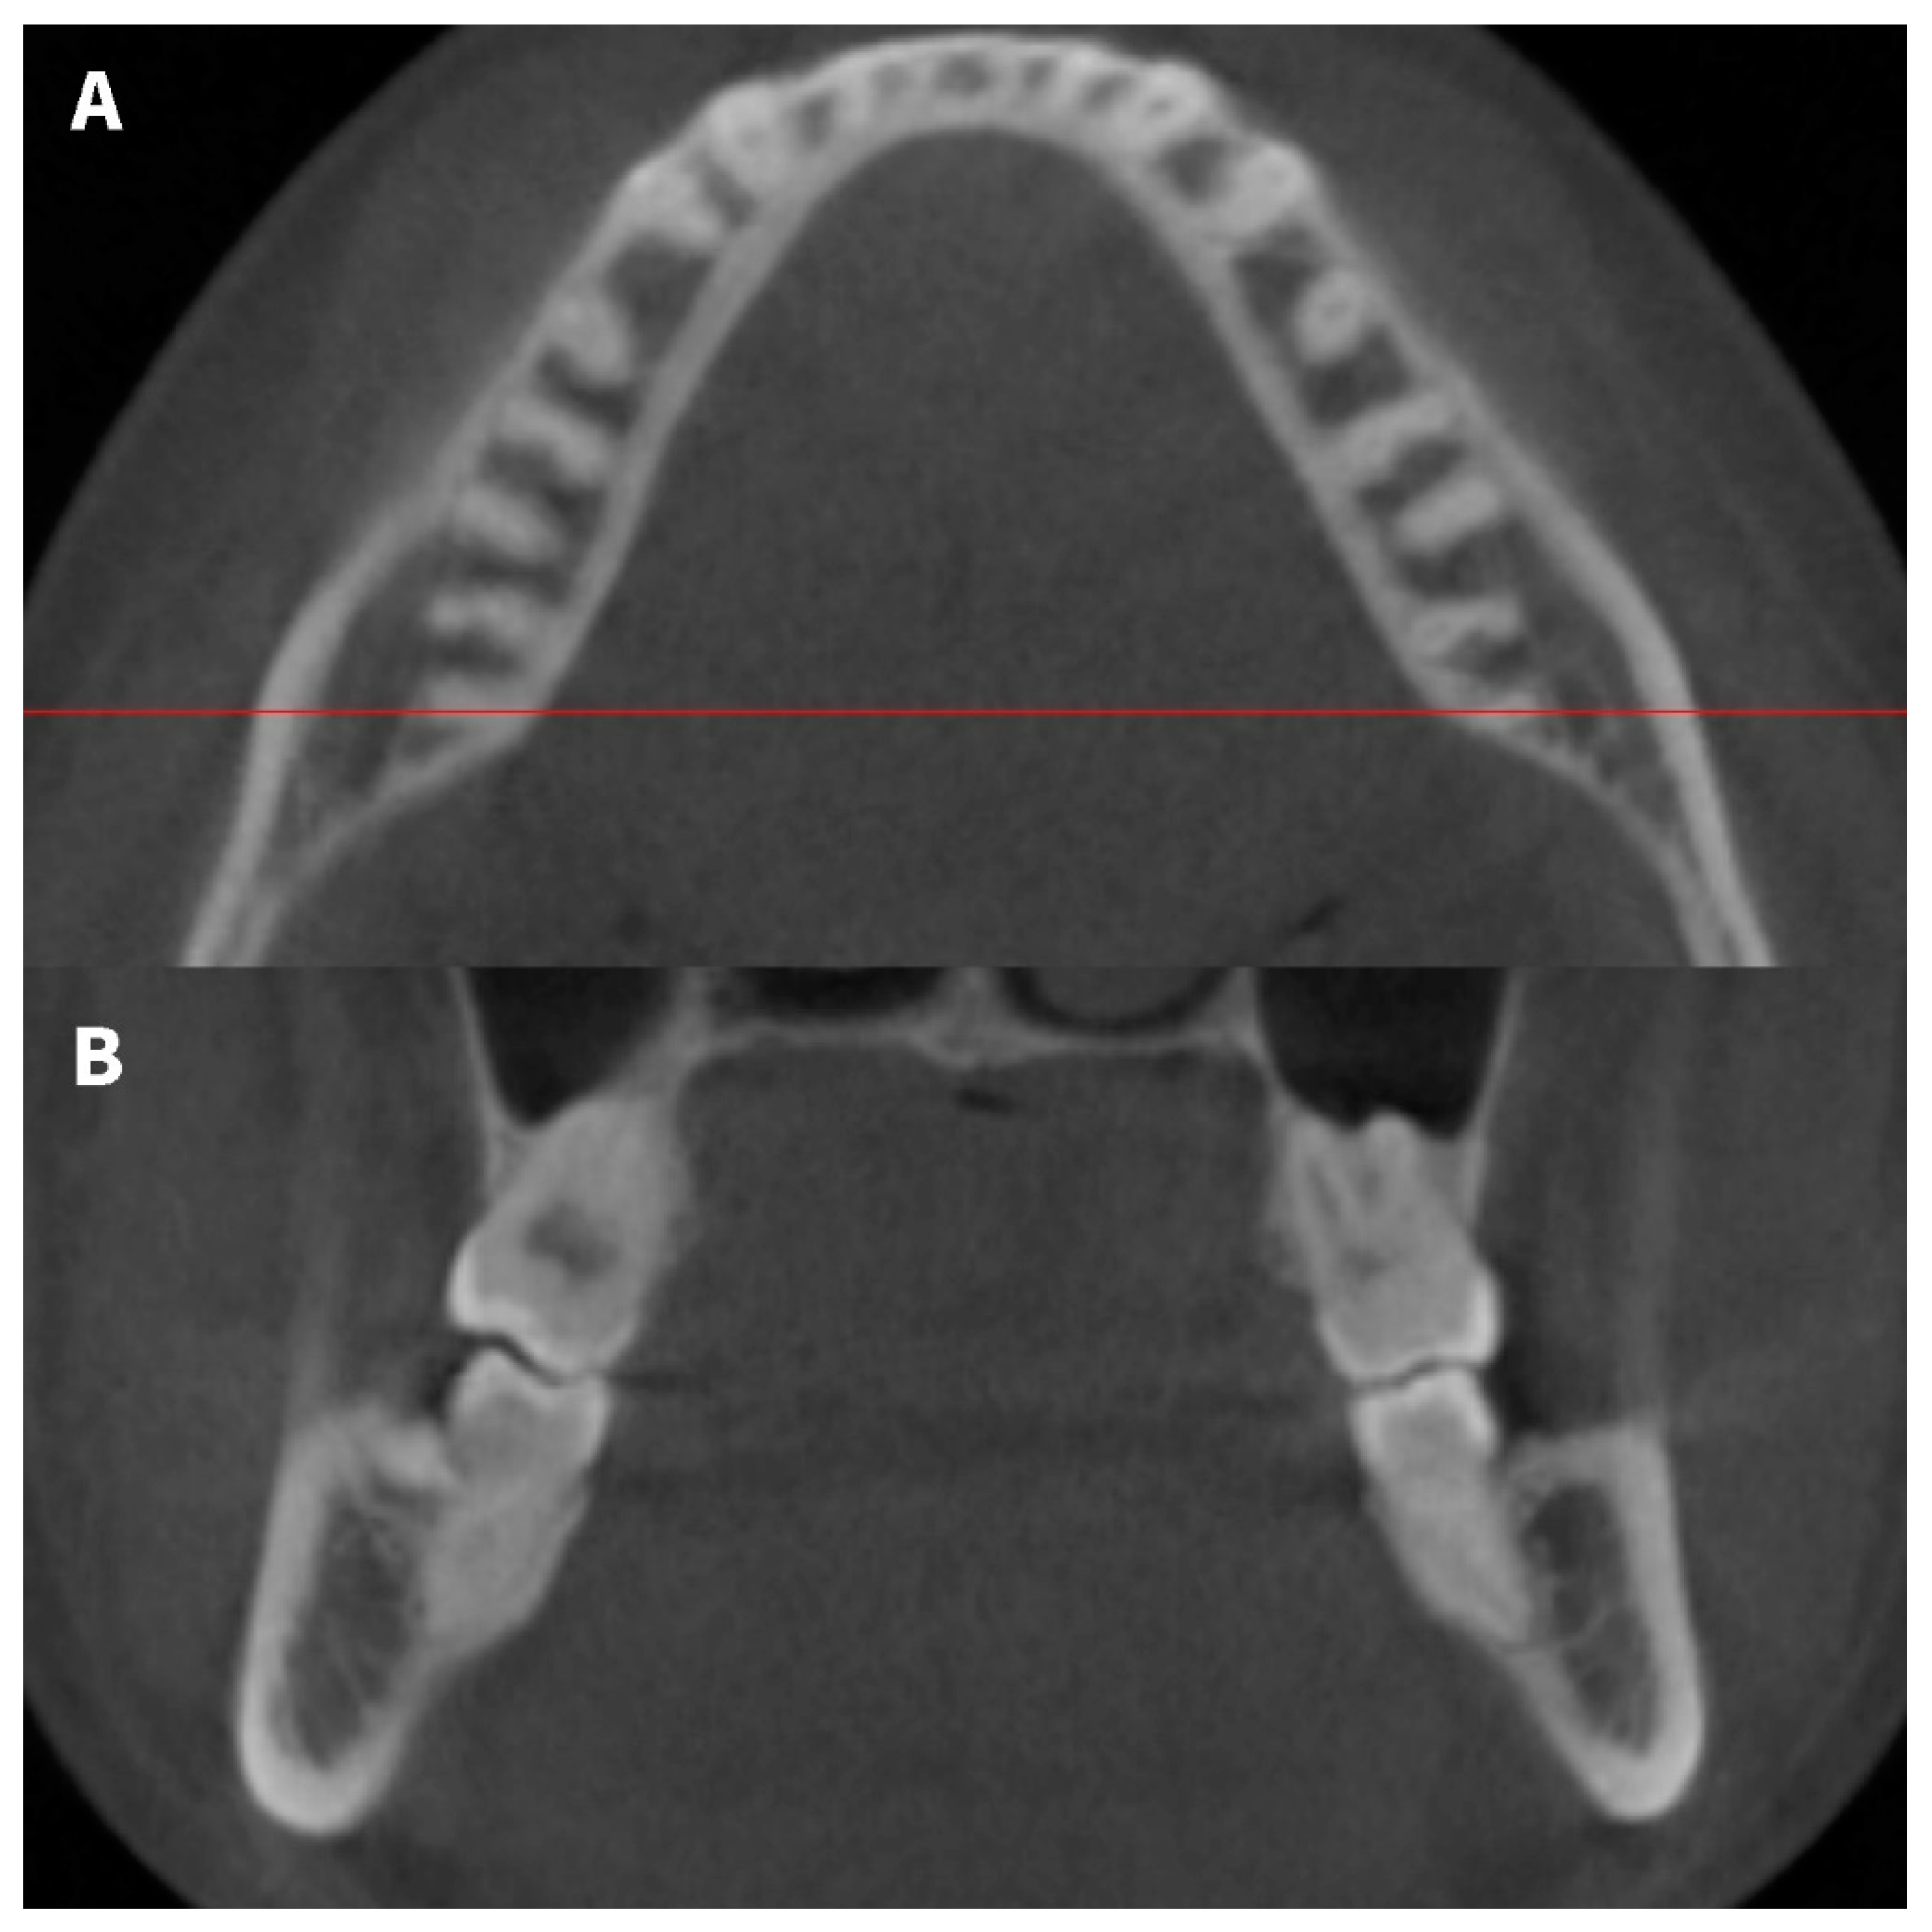

We observed that the distance between the mandibular molar roots and the outer surface of the mandibular lingual cortical bone decreased from mesial to distal. This finding was consistent with the observations of Aljarbou et al. [3]. The distance between the mandibular first molar roots and the lingual cortical bone increased from the cervical to the apex. In contrast, there was no significant difference in the distance between the mandibular second molar roots and the lingual cortical bone relative to the root level. In addition, the lingual cortical bone of the distal part of the second molars shows an S-shaped curve, which is in contrast to the lingual cortical bone near the first molar that is parallel to the dental arch. (Figure 5). The morphology of the lingual cortical bone is thought to be related to the location of the mylohyoid line. Aoki et al. reported that the mylohyoid line is 16 mm away from the mandible lower edge in the distal root area of the mandibular second molars [8]. Considering the mean D7MP measured in our study was 13.44 mm, the distal roots of the mandibular second molars appear to be located close to the mylohyoid line. Overall, these findings suggest that second molars are more likely to be a problem than first molars during distalization or intrusion of the mandibular posterior teeth.

Figure 5.

CBCT multiplanar reconstruction images showing contacts between distal roots of mandibular second molars and the lingual cortical bone. (A) axial view, (B) coronal view.